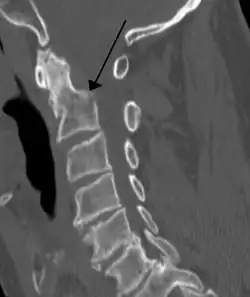

Radiographic detection

On CT scan or X-ray, a cervical fracture may be directly visualized. In addition, indirect signs of injury by the vertebral column are incongruities of the vertebral lines,[7] and/or increased thickness of the prevertebral space:[8]